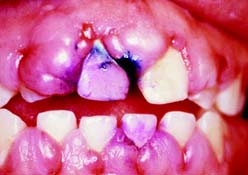

This class (Figs. 1-29 and 1-30) is characterized by moderately compromised location and extent of edentulous areas in both arches, abutment conditions necessitating localized adjunctive therapy, occlusal characteristics necessitating localized adjunctive therapy, and residual ridge conditions.

Fig. 1-29 Class II patient. This patient is categorized as Class II because he has edentulous areas in two sextants in different arches. A, Frontal view, maximum intercuspation. B, Right lateral view, maximum intercuspation. C, Left lateral view, maximum intercuspation. D, Occlusal view, maxillary arch. E, Occlusal view, mandibular arch. F, Frontal view, protrusive relationship. G, Right lateral view, right working movement. H, Left lateral view, left working movement. I, Full-mouth radiographic series.

(From McGarry TJ, et al: Classification system for partial edentulism. J Prosthodont 11:181, 2002.)

Fig. 1-30 Class II patient. The patient is categorized as Class II because one sextant exhibits three defective restorations with an esthetic component. Additional variables of gingival architecture and individual tooth proportions increase the complexity of diagnosis. A, Frontal view, maximum intercuspation. B, Right lateral view, maximum intercuspation. C, Left lateral view, maximum intercuspation. D, Occlusal view, maxillary arch. E, Occlusal view, mandibular arch. F, Panoramic radiograph.

(From McGarry TJ, et al: Classification system for the completely dentate patient. J Prosthodont 13:73, 2004.)